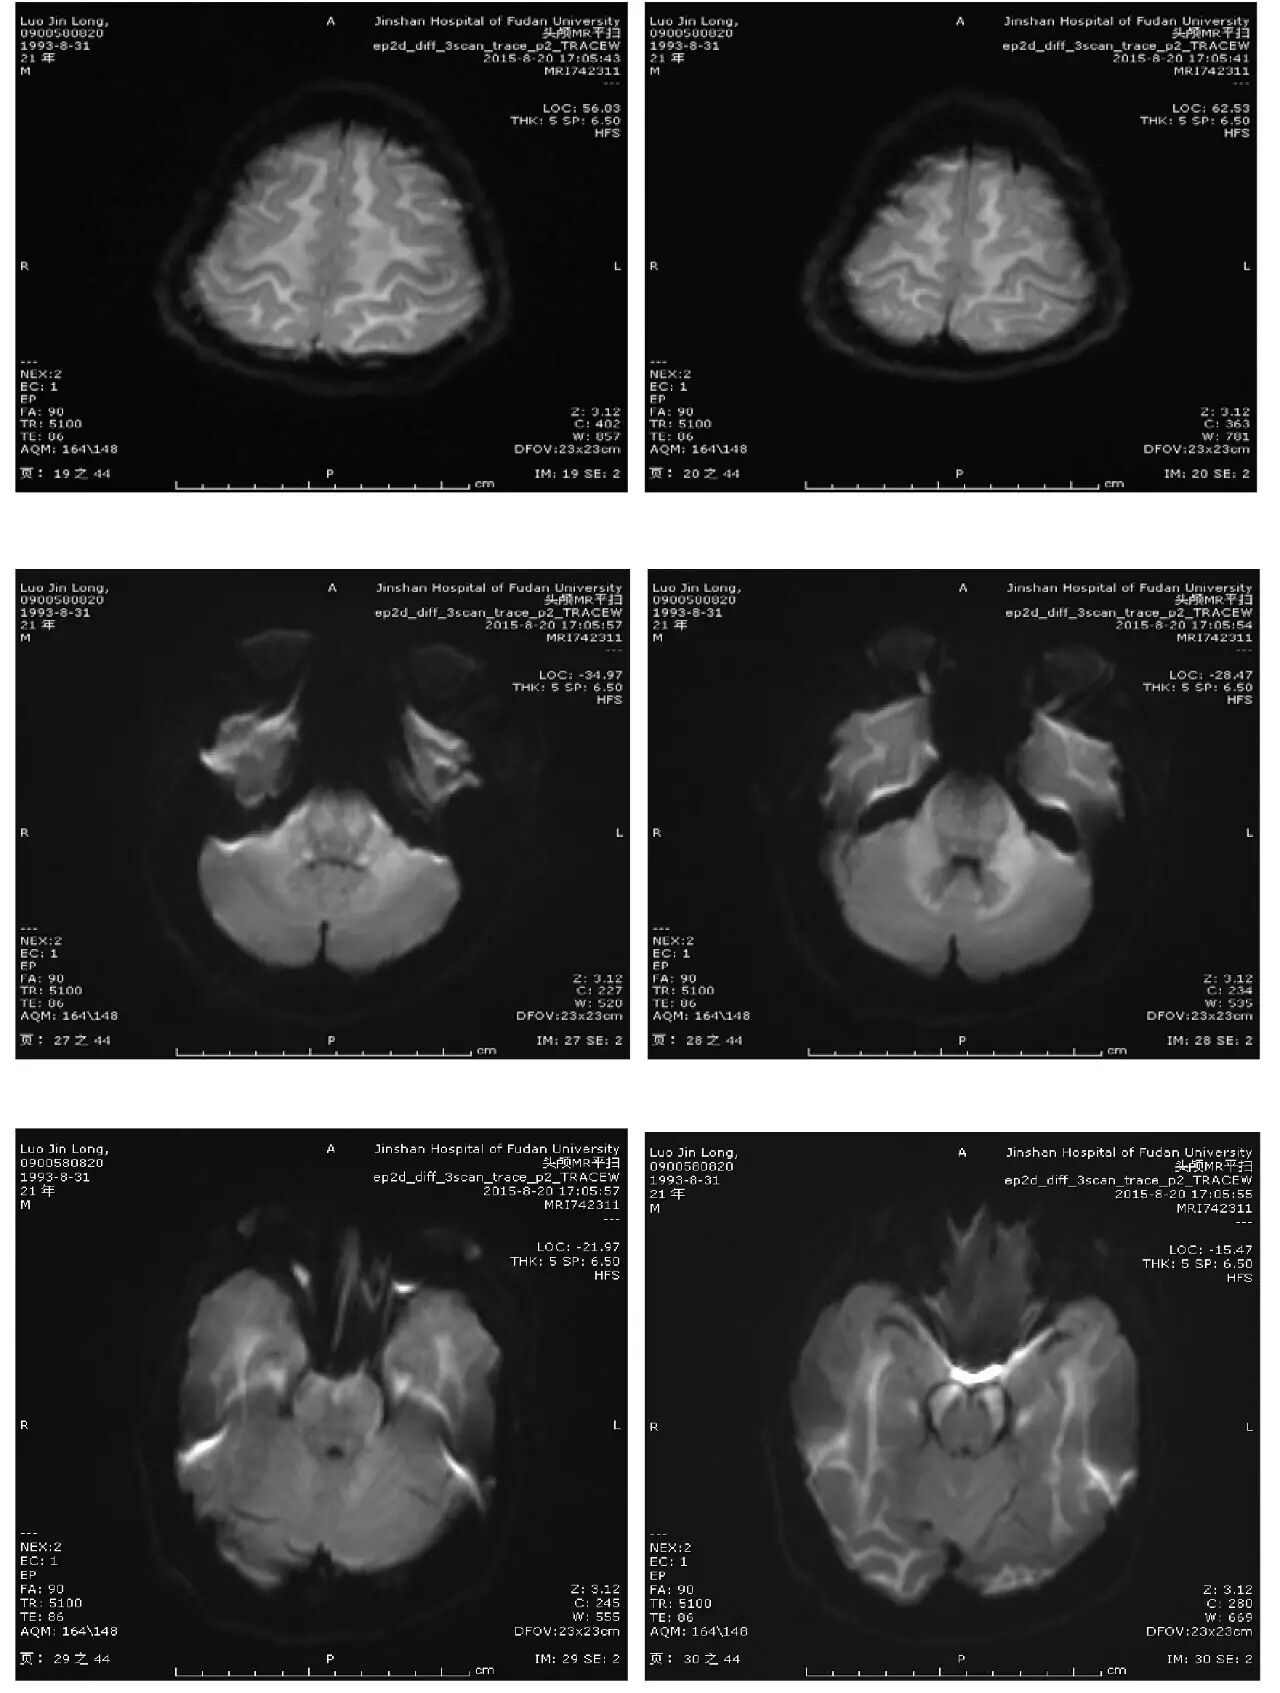

主诉:头痛、反应迟钝、口齿不清4天

现病史:头中线部位钝痛,反应迟钝,口齿不清,无发热,无恶心、呕吐,无饮水呛咳,四肢乏力。无麻木不适。2天后出现视物模糊。外院头颅CT:两侧大脑半球低密度灶。

(点击查看高清图)